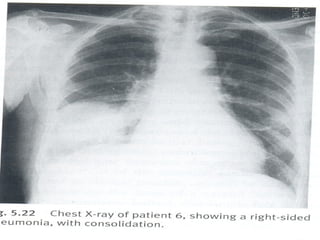

Imagem

Radiografia simples de tórax

- Póstero-anterior

CONDENSAÇÃO

 INSPEÇÃO ESTÁTICA– SEM ABAULAMENTOS OU

RETRAÇÕES

 INSPEÇÃO DINÂMICA – DIMINUIÇÃO DA

ESPANSÃO

 PALPAÇÃO- DIMINUIÇÃO DA EXPANSIBILIDADE

 FTV – AUMENTADO

 PERCUSSÃO- MACICEZ OU SUBMACICEZ

 AUSCULTA- ESTERTORES CREPITANTES E/OU

SUB.

 BRONCOFONIA AUMENTADA, PECTORILÓQUIA

E SOPRO TUBÁRICO